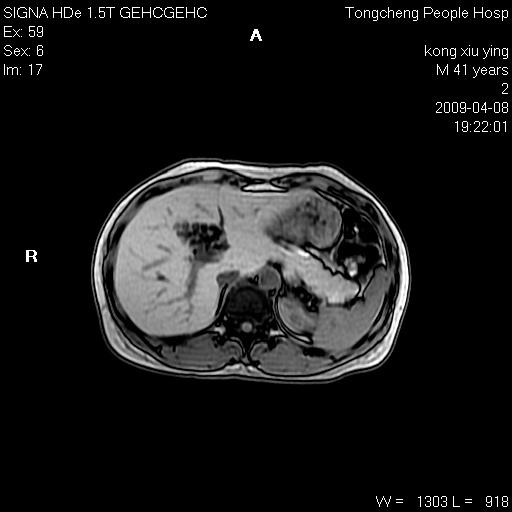

标题: CL1008:【经典】胆囊石榴籽样结石。

女,41岁。健康体检——彩超提示:胆囊显示不清。平素健康,无不适感。

腹部mr扫描及mrcp,图像如下:

标题: 胆囊阴性结石ct图片

好啊!我有ct的插进来啊,楼主请允许噶。